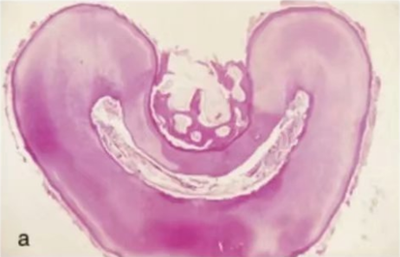

在白種人中,下頜第一磨牙主要為雙根—近中根和遠(yuǎn)中根,但其中根管形態(tài)各異。根據(jù)Vertucci 的分類,下頜第一磨牙中 59%的近中根在根尖處為獨立的雙根管,28%為兩根管融合成單根管單根尖孔,12%為單根管,1%為三根管(8,9)(圖 11a,b)。在另一項研究中,下頜磨牙的近中中根管(MM)發(fā)生率在 1%至 7%之間變化(92-99)。三個近中根管可以是獨立的(92-95)或融合稱為兩個根管,在根尖有兩個根管口(96-99)。

在歐洲人中,下頜第一磨牙的遠(yuǎn)中根大約 70%為單根管。15%為雙根管融合為單根管,5%為兩個獨立的根管,8% 為單根管分為雙根管,2%為單根管分為雙根管并再次于根尖1/3融合為單根管(8)(圖12a-b)。